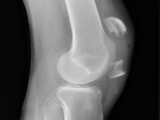

DJD Knee

DJD Knee